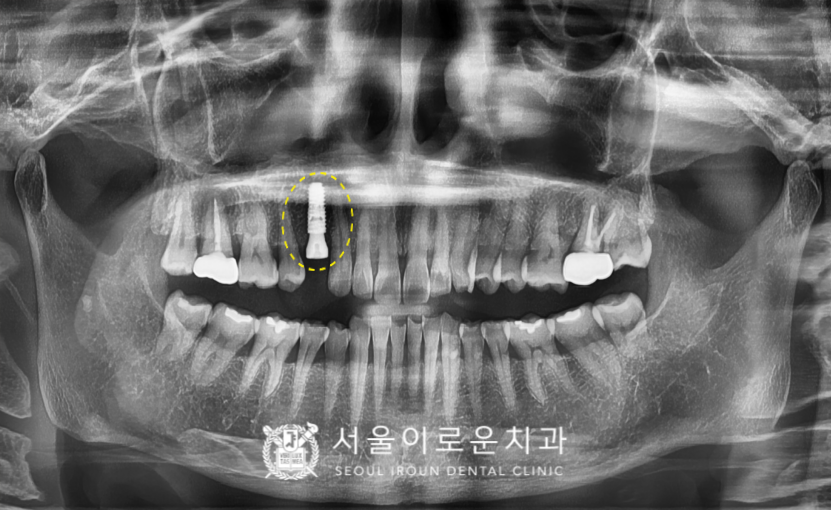

그리고 임플란트 식립 후 2달 반 후에

뼈와 임플란트가 단단하게

결합이 잘 되었는지 확인하는

osstell beacon이라는 장비를 이용하여

골유착정도(isq)를 측정하였고,

안정 값을 확인한 뒤

보철 과정까지 마무리해 드렸습니다.

오른쪽 위 작은 어금니(#14) 부위의

임플란트 과정이 마무리되고 얼마 뒤

임플란트 식립 후 2달 반 후에

골유착 정도(isq)를 측정하여

보철물 과정을 진행하였습니다.

2개의 임플란트와 더불어

치경부 마모증 부위엔

레진치료를 모두 종결하였습니다!